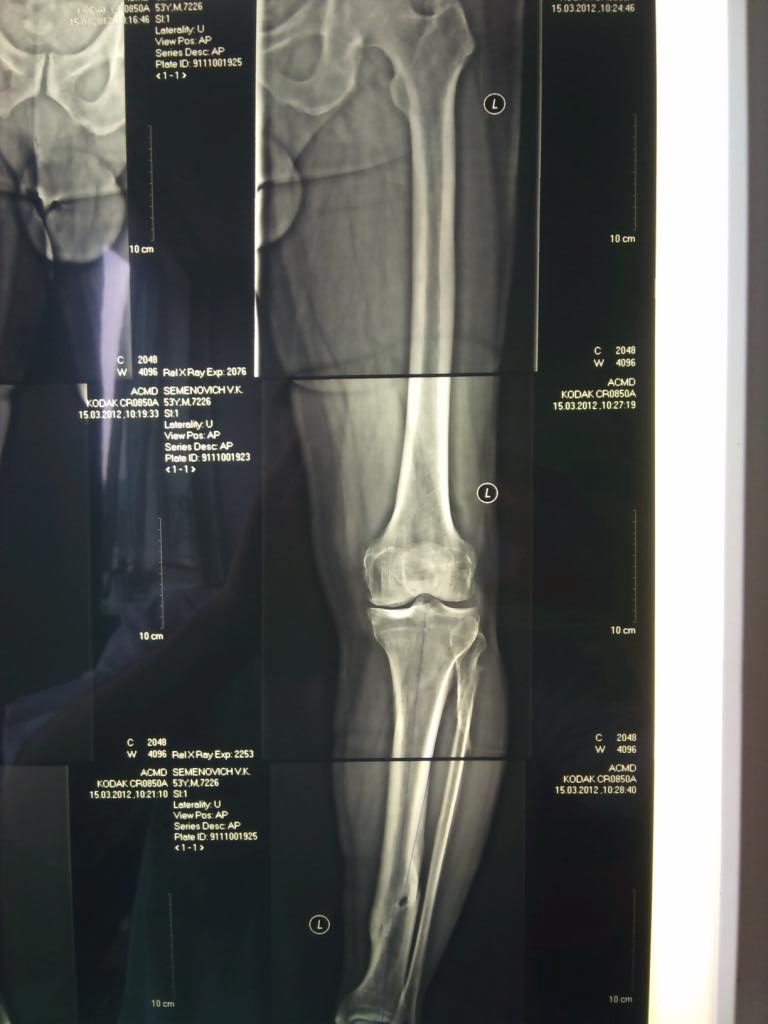

Обратился пациент, 53 года, среднего типа телосложения, довольно активного образа жизни. Жалобы - на боли в обеих коленных суставах после физических нагрузок. В анамнезе, 20 лет назад, былли переломы обеих голеней,лечился консервативно.

1.что делать - коррегирующую остеотомию (вальгизирующую) или одномыщелковое эндопротезирование?

2.нужна ли перед этим (одномоментно?) коррекция давно консолидированных переломов голеней?